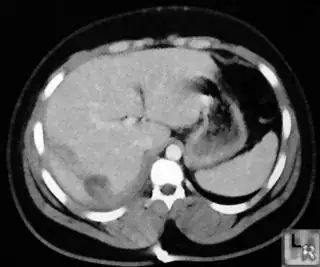

Here is other sample image with rgb range varying from 110 to 180 sample image 3.